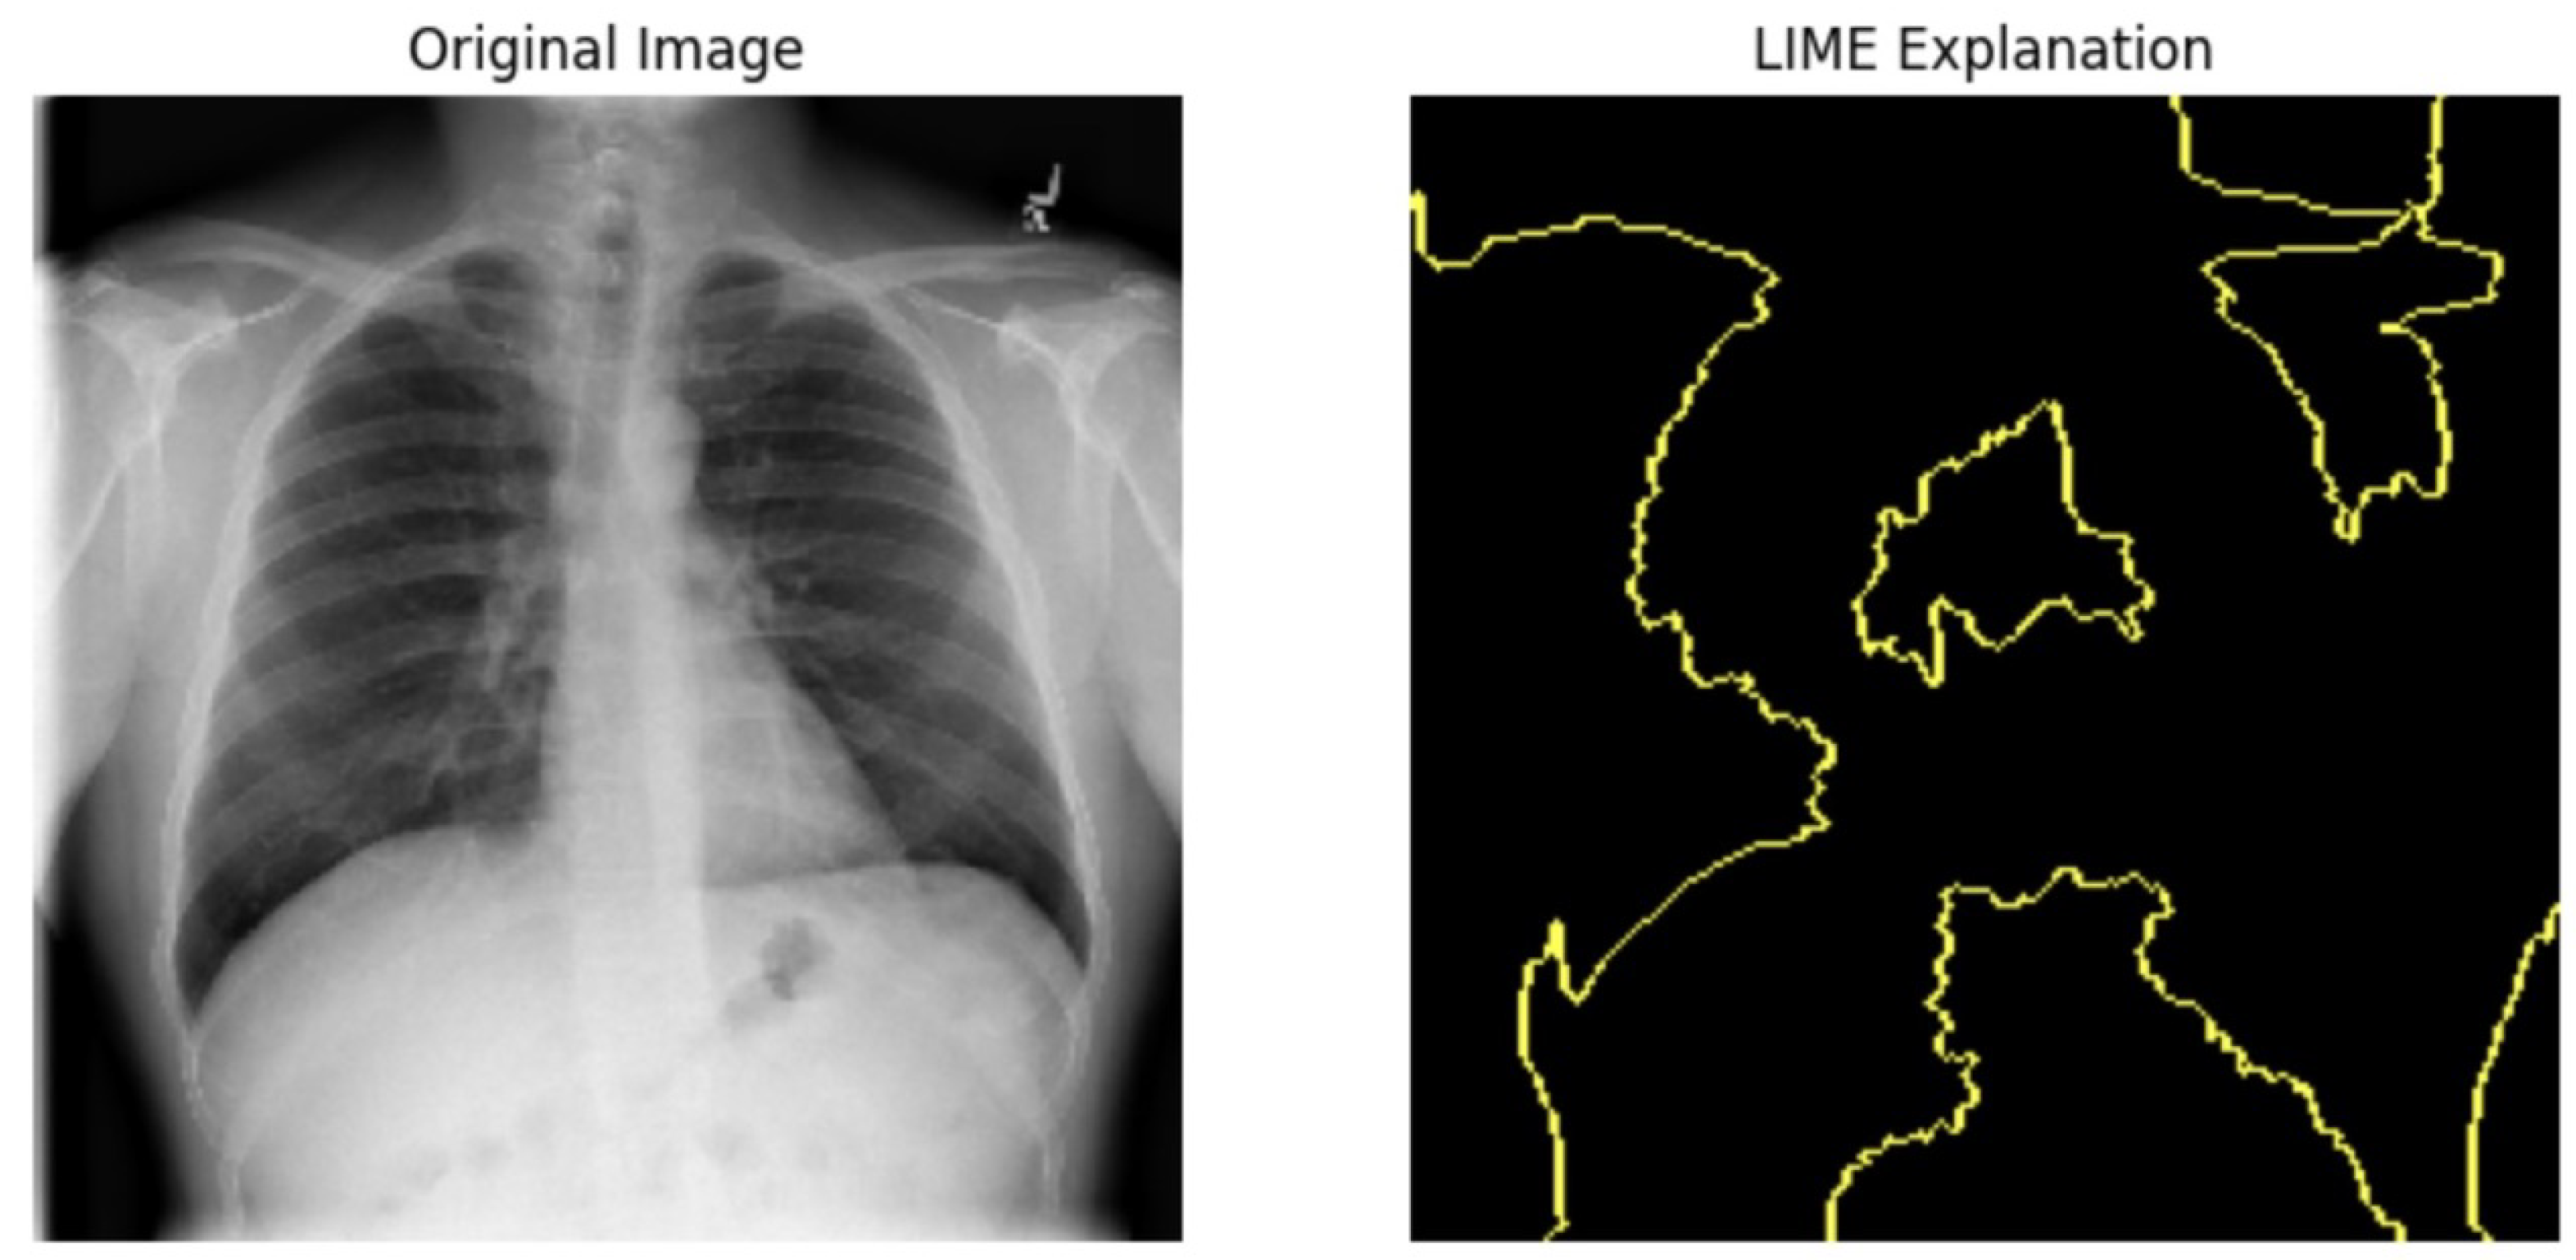

5.4.1. Local Interpretable Model-Agnostic Explanations for Clinical Validation

We applied scientific analysis on a random 7 sample, which was provided by the clinical specialist. The LIME Analysis for Image Data (a), (b), (c), (d), (e), and (f) is in Figure 22, Figure 23, Figure 24, Figure 25, Figure 26 and Figure 27. There are two parts of LIME analysis from the provided chest X-ray images to detect the disease area. Original Image and LIME explanation;

• Original Image: The patient’s thoracic cavity. It displays the typical anatomical structures of the chest, including the lungs, ribs, and heart.

• LIME Explanation: The result of applying LIME to the chest X-ray image. The yellow boundaries indicate the regions of the image that were most influential in the model’s decision-making process when determining whether the image indicated a particular condition. In this context, these regions are the parts of the X-ray that the AI model considered most important for making its diagnostic prediction.

The analysis very useful for clinicians to understand the model’s behavior and ensure that it aligns with medical expertise. The use of LIME helps in making the AI model’s interpretability decisions more transparent and interpretable. It allows medical professionals to verify whether the AI’s focus areas correspond to clinically significant regions. It also enhanced diagnostic capability of understanding which parts of the images in the AI model in refining the model further and ensures that it makes accurate and reliable predictions. This is particularly crucial in medical diagnostics where interpretability and accuracy are paramount.

Figure 22. LIME Analysis for Image Data (a) on original image to LIME explanation.

Jpm 14 00856 g022